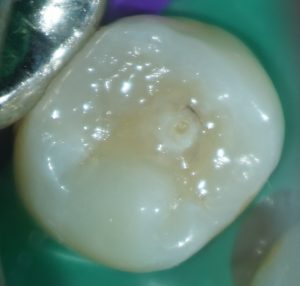

たとえば、この症例はいかがでしょう。

中心結節がある症例では、中心結節に歯髄が嵌入していることが知られています。

この症例を普通に治そうとするとインレーになりますよね。

しかし、通法の形成ではイスムスを形成しているときに露髄してしまうかもしれません。

私はこういった症例の治療をする場合、う蝕を取り除き、

露髄していないことを確認したうえで、コンポジットレジンで修復することがほとんどです。

これを自由診療で行っています。

患者さんは、歯髄を失わなくて済むので自由診療を選択したことをとても喜んでくれます。